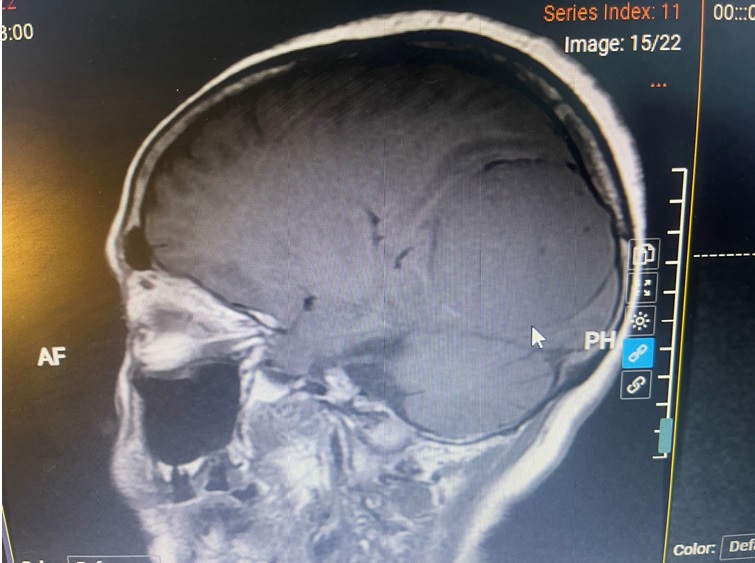

Trường hợp thứ hai là bệnh nhân N.T.L (75 tuổi), nhập viện trong tình trạng đau đầu kéo dài, nói khó. Kết quả chụp cộng hưởng từ sọ não xác định có khối u nội sọ lớn (6x6cm) vùng thùy đỉnh chẩm trái, nghi là u màng não, chèn ép cấu trúc não quan trọng.

Hình ảnh khối u não kích thước lớn trước mổ